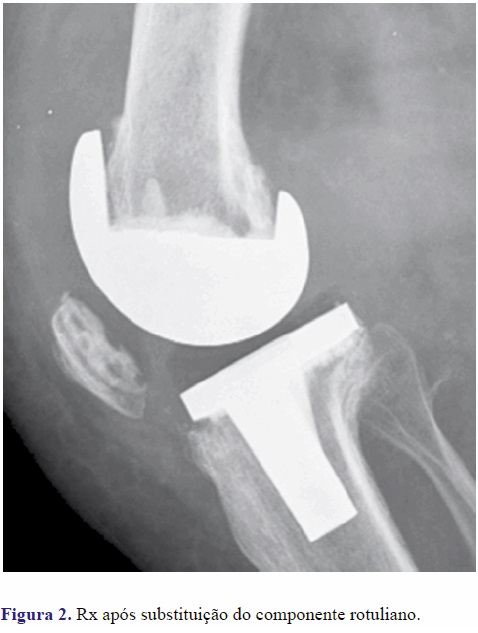

Não foi documentado nenhum caso de revisão cirúrgica por infecção. No grupo B 2 doentes foram reintervencionados para realinhamento do aparelho extensor e 5 reintervencionados para substituição da rótula (Figuras 1 e 2). Nenhum doente do Grupo A foi revisto até à data do estudo.